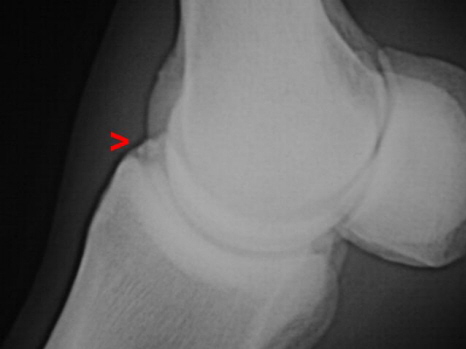

Chip Fesselgelenk